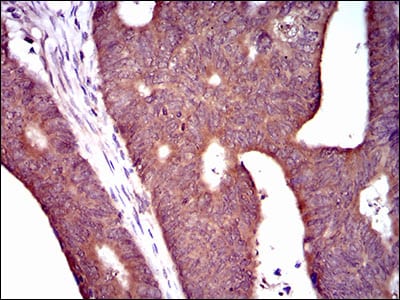

分类: 科研抗体货号: 30464P别名: PDE1B1; PDES1B应用: WB,IHC,FCM反应种属: Human,Rat